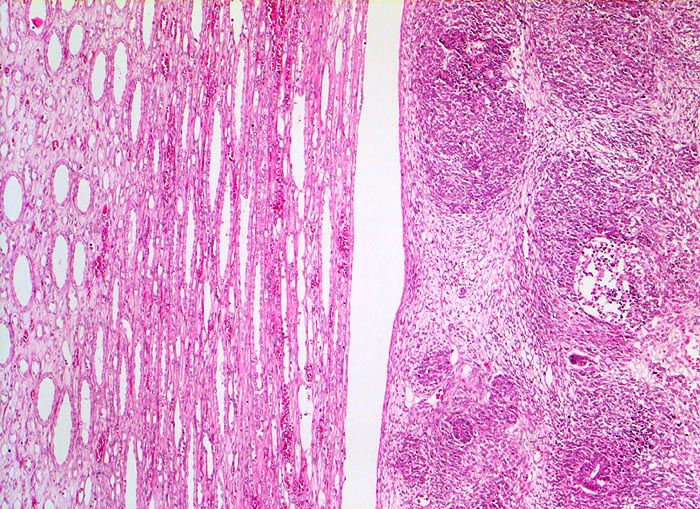

PathoPic ID 5179 - Wilms-Tumor

Wilms-Tumor

maligner Tumor

Niere

Paidopathologie

Das Nierenmark (links) wird durch den expansiv wachsenden scharf begrenzten Tumor (rechts) lediglich

komprimiert, nicht aber infiltriert.

Graubrauner scharf begrenzter weicher Tumor mit fokalen Nekrosen und Einblutungen.

Palpabler Tumor im linken Hemiabdomen. Makrohämaturieepisode.

Histologie

50